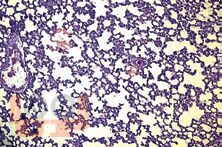

В книге обобщены современные представления об этиологии, патогенезе сепсиса и системной воспалительной реакции. Отдельные главы посвящены современным тенденциям в терапии сепсиса. В монографии подробно рассматриваются вопросы применения и различных вариантов экстракорпоральной детоксикации у больных с сепсисом.